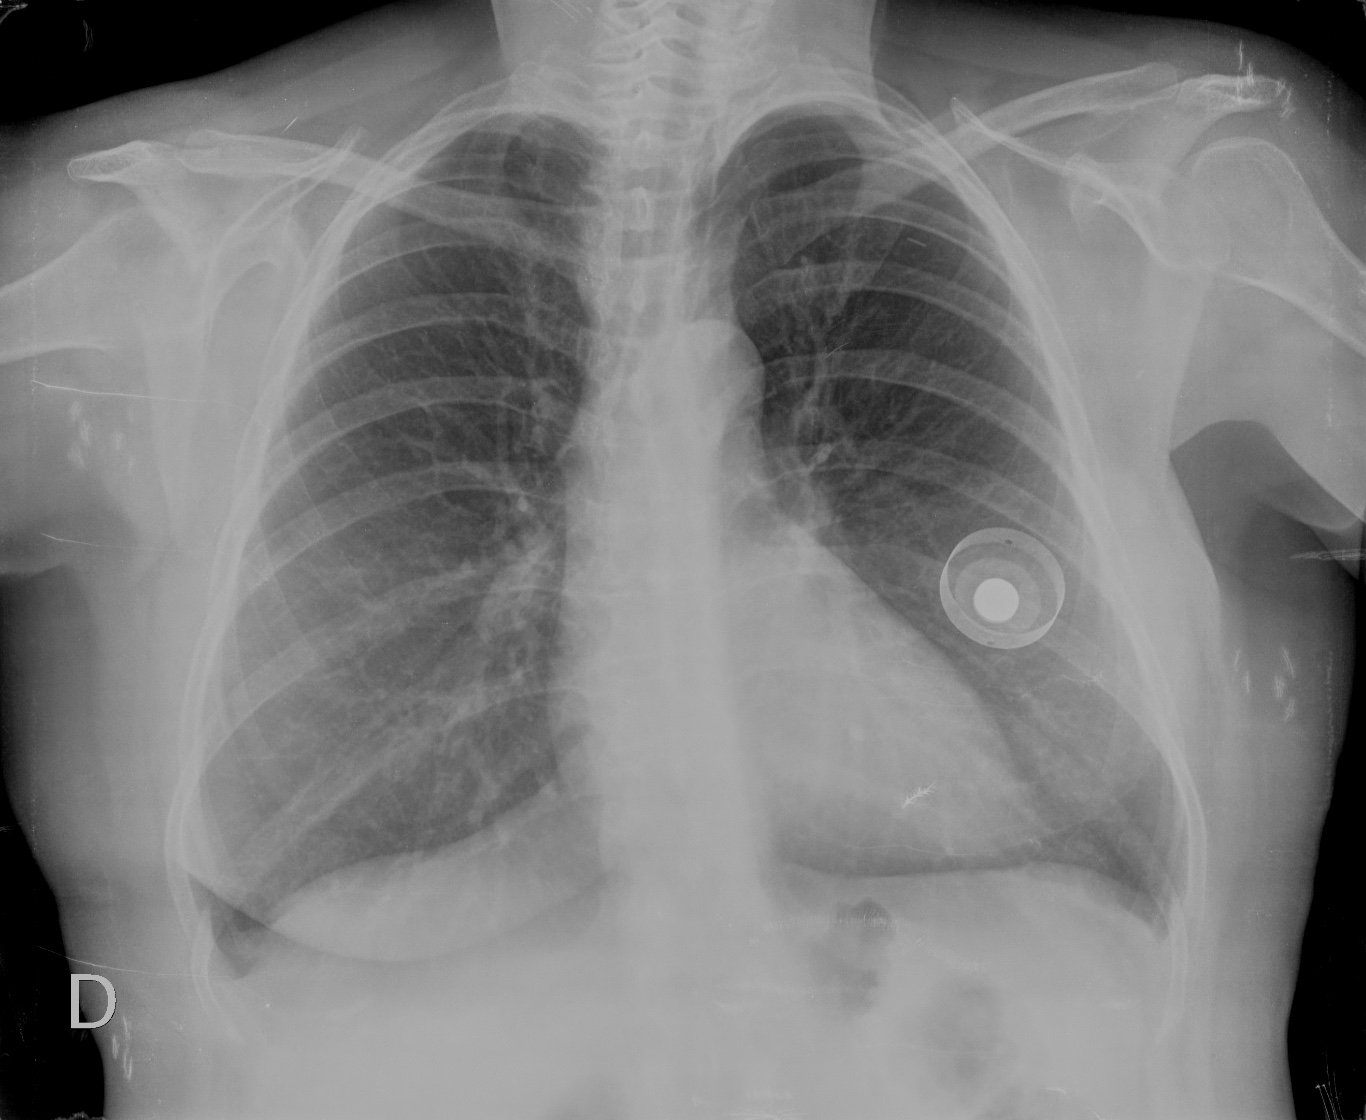

CASO: Revisión en paciente con tratamiento quimioterápico.

Hallazgos:

- Reservorio subcutáneo en hemitórax izquierdo con bucle del catéter a nivel subclavio. Extermo del catéter en vena cava superior.

CASO: Revisión de cáncer mamario.

- Parénquimas pulmonares y silueta cardiomediastínica sin alteraciones.

- Expansor mamario proyectado sobre silueta mamaria izquierda.

Un expansor es una envoltura vacía con una válvula incorporada que se usa tras una mastectomía. Esa envoltura se llena gradualmente a través de la válvula con solución salina con la finalidad de estirar el tejido y formar una cavidad y así proporcionar el espacio óptimo para un implante mamario futuro.